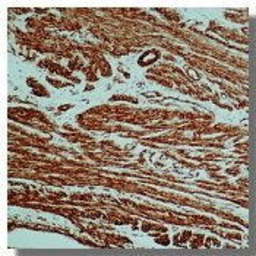

IHC-P analysis of human leiomyoma tissue using GTX18147 alpha Smooth Muscle Actin antibody [0.N.5].